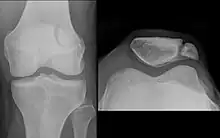

The upper three-quarters of the patella articulates with the femur and is subdivided into a medial and a lateral facet by a vertical ledge which varies in shape.

In the adult the articular surface is about 12 cm2 (1.9 sq in) and covered by cartilage, which can reach a maximal thickness of 6 mm (0.24 in) in the centre at about 30 years of age. Owing to the great stress on the patellofemoral joint during resisted knee flexion, the articular cartilage of the patella is among the thickest in the human body.

Variation

The upper three-quarters of the patella articulates with the femur and is subdivided into a medial and a lateral facet by a vertical ledge which varies in shape. Four main types of articular surface can be distinguished:

- Most commonly the medial articular surface is smaller than the lateral.

- Sometimes both articular surfaces are virtually equal in size.

- Occasionally, the medial surface is hypoplastic or

- the central ledge is only indicated.